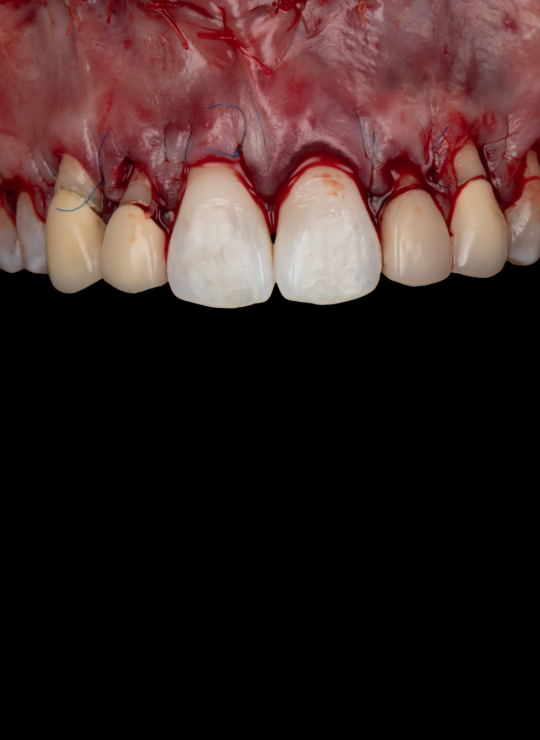

Acquire comprehensive skills in osseous surgery, instrumentation, suturing techniques, and flap reflection for precise and efficient crown lengthening procedures.

Surgical techniques for aesthetic crown lengthening: flap design, bone recontouring, and suturing

Surgical techniques for posterior crown lengthening: flap design modifications, osseous recontouring, suturing